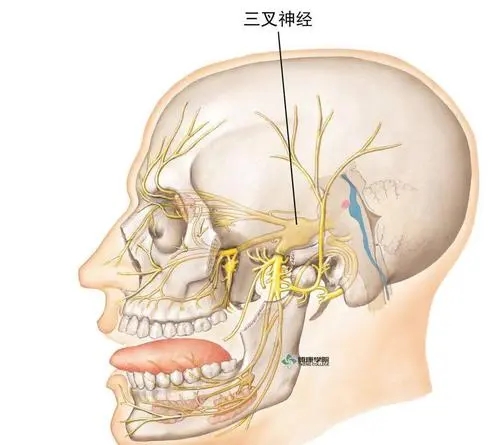

什么是三叉神经痛?

三叉神经痛又称“天下第一痛”,主要以单侧头面部反复发作、短暂性、电击样、烧灼样、刀割样等疼痛为特点,突发突止,一般历时几秒到数分钟,通常说话、咀嚼、洗脸、刷牙、吹风等时可诱发,常常累及三叉神经一个或多个分支。严重影响患者生活质量。具体病因目前不清楚,考虑:1.和神经伴行动脉血管关系太近,动脉搏动刺激神经,诱发疼痛。2.考虑神经自身病变引起。